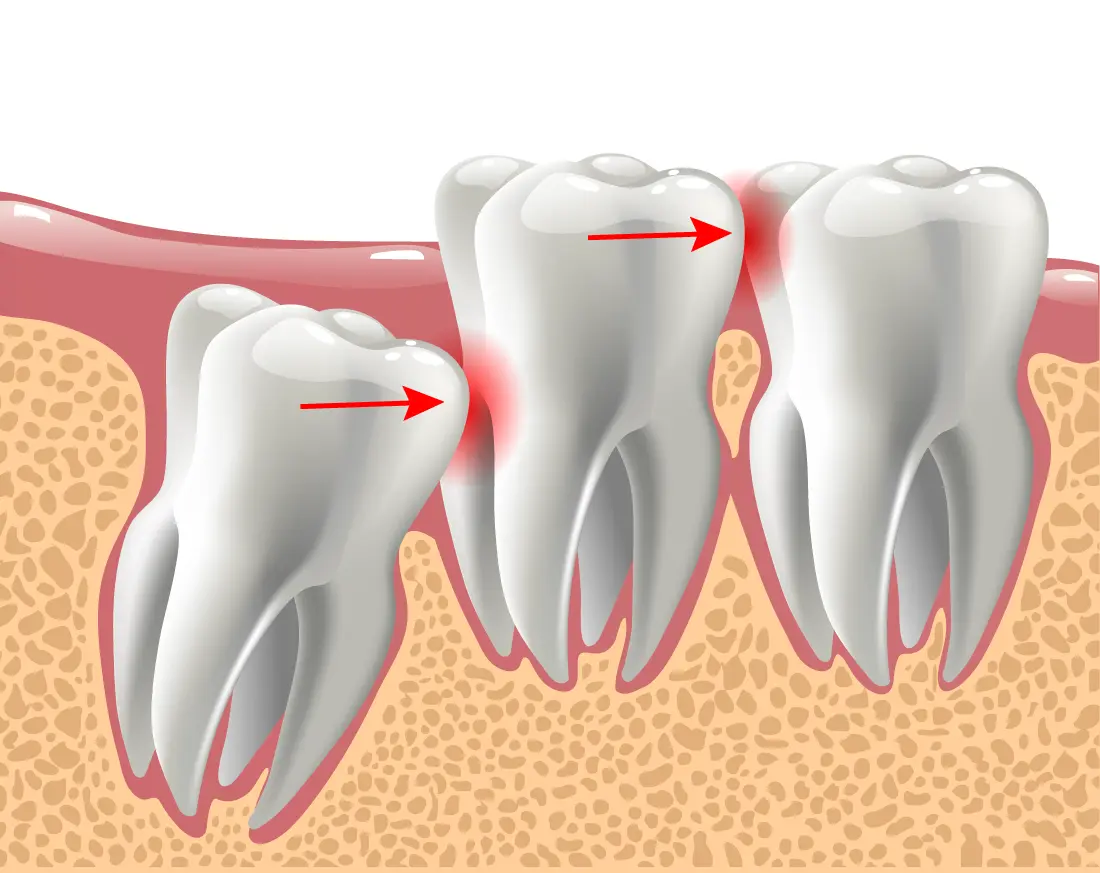

Wisdom teeth often have to be extracted to ensure the rest of your teeth stay healthy. Most wisdom teeth erupt misaligned, which can cause tooth crowding and disruption in your teeth and gums. This is not only painful but can make oral hygiene more difficult. Another common reason for wisdom teeth extraction is a partial eruption. This encourages bacteria to accumulate in the pockets of your gums, putting you at risk for gum disease, infection, and tooth decay. That being said, sometimes wisdom teeth don’t always need to be removed. If your wisdom teeth erupt properly aligned and don’t impact your other teeth, your doctor may not recommend extraction. But generally, wisdom teeth need to be removed to preserve a healthy smile.